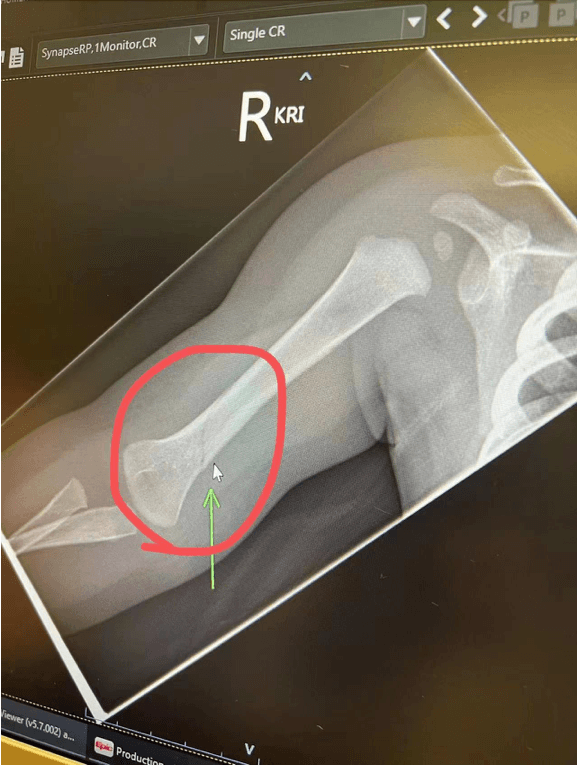

7月20 日张丹阳告诉我孩子手臂抬不起来,我和爸爸立即前往医院,经医生检查,发现孩子右侧大臂骨折,并明确表明,骨头是很坚硬的,如果不是受到很大外力不会导致骨折后child protection, social work,police等一些组织到访询问情况,张丹阳避重就轻,不答造成伤害的真实原因,导致无法找致害因素。后多次追问承认宝宝多次从床上滚下,孩子也被相关机构隔离带走,此人也已被各大华人媒介曝光。